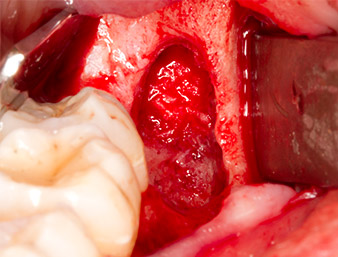

Dopo l'anestesia tronculare e l'anestesia locale, il sito operatorio è stato aperto e il tessuto molle esposto per l'accesso retromolare boccale (Fig. 3).

Il tessuto al di sopra del residuo di radice non era completamente ossificato ed era costituito per la maggior parte da tessuto di granulazione modificato dall'infiammazione (Fig. 4).